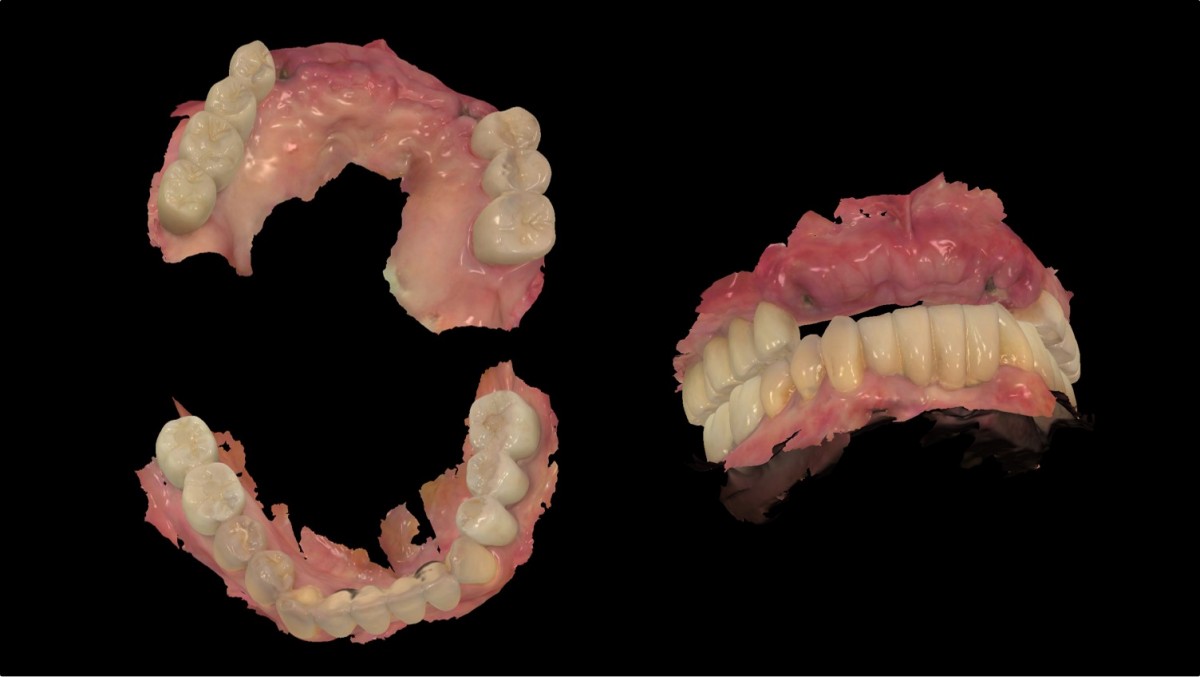

Anterior implant placement with Arum implant system in the maxilla.

The patient is scheduled

for the implant and general prosthetic restoration in various parts. First of

all, the vertical stop is completed by several prostheses in the posterior

region, and the final stage of intraoral restoration is to proceed with an

anterior implant installation.